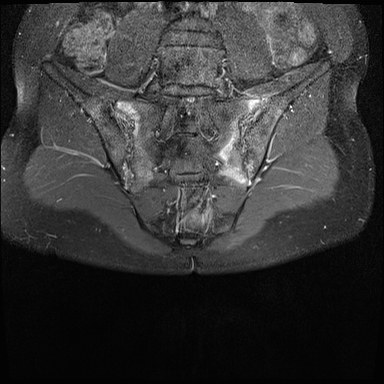

MRI

MRI chuỗi xung T1W sau tiêm thuốc tương phản từ của cùng bệnh nhân cho thấy bờ khớp cùng chậu không đều do bào mòn.

Có ngấm thuốc ở xương dưới sụn và phù nề tủy xương.

Không có tràn dịch khớp.

Thuốc tương phản từ tiêm tĩnh mạch không nhất thiết phải sử dụng để chẩn đoán viêm khớp cùng chậu.

Cuộn qua các hình ảnh MRI và so sánh với các dấu hiệu trên X-quang (hình ảnh cuối cùng).